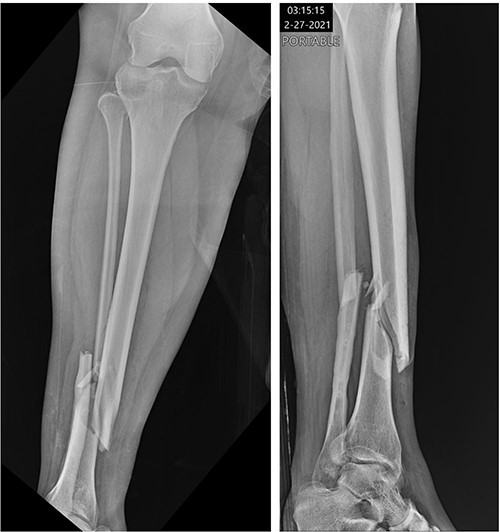

At 2 weeks post-op, the patient was managing pain well, and she demonstrated appropriate range of motion and strength. At 6-week follow-up, however, she complained of diffuse, painful grinding in the right knee which impaired her ability to ambulate. Physical exam revealed audible and palpable crepitus in the knee as well as tenderness to palpation at the medial and lateral joint lines. Radiographs demonstrated unchanged alignment of the tibia fracture (Fig. 3). Multiplanar T1 and T2 MRI without contrast revealed a large full-thickness defect on the lateral femoral trochlea measuring 1.8 cm in diameter with a loose chondral fragment in the superior medial joint space (Fig. 4).

Radiographs at 6 weeks post-op demonstrating unchanged alignment of the distal tibia/fibula fracture.